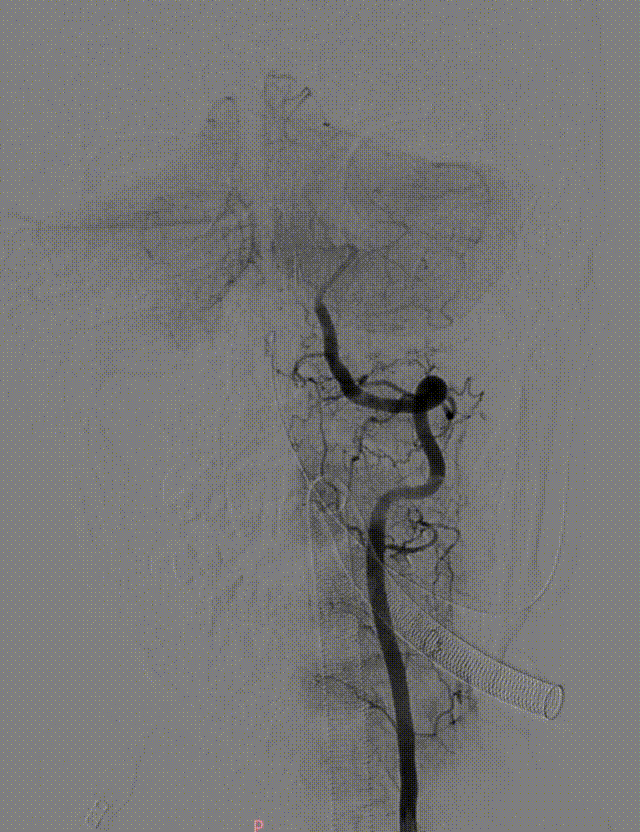

微导丝携带微导管至右侧大脑后动脉P3段,抽拉结合取栓一次见右侧大脑后动脉再通。

微导丝携带微导管至左侧大脑后动脉P3段,抽拉结合取栓一次见左侧大脑后动脉再通。

左侧大脑后动脉P1段发白,观察20min较前好转,血流状态维持良好,结束手术。